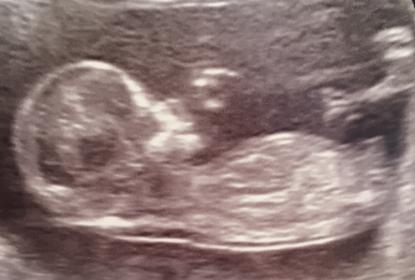

I'd say boy too. First pic is short but flat, but the second nub is angled with stacking so looks boyish.

Boy based on major stacking in 2nd pic.